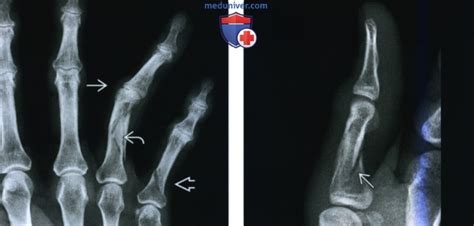

Перелом пальца на руке - симптомы и признаки, л...

Перелом мизинца на руке: признаки, лечение и ре...

Перелом мизинца на руке: симптомы, сколько зажи...